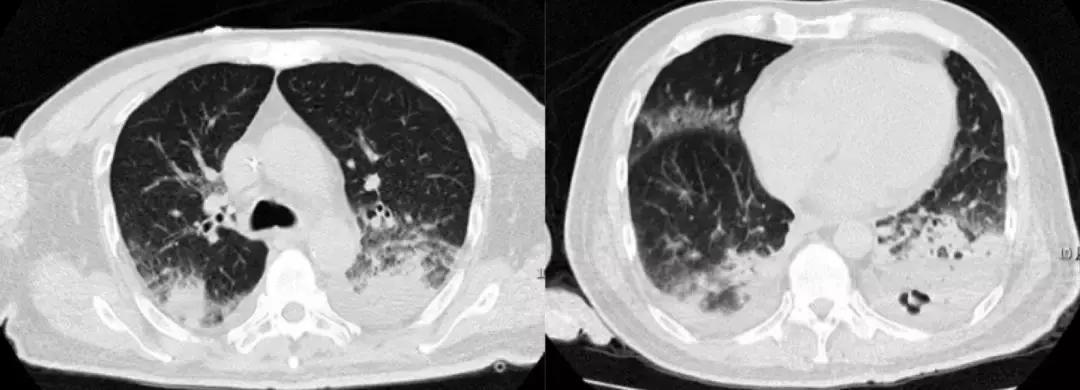

典型病例 5

16岁,男,主因:发热1周,呼吸困难1天入院,既往臀部皮肤疖肿,输尿管结石,体外碎石术后,输尿管D-J管置入术后。泰能联合万古霉素治疗无效。

支气管镜结果:H7N9。仔细追问患者病史:仅仅有经过养鸡场。

经验教训

您能根据影像判断患者是病毒感染吗?但是在广谱抗生素抗感染治疗无效的ARDS患者,一定警惕病毒感染。